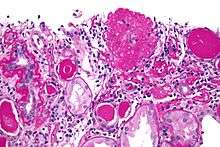

The individual components of the name refer to the appearance of the kidney tissue on biopsy: focal—only some of the glomeruli are involved (as opposed to diffuse), segmental—only part of each glomerulus is involved (as opposed to global),[4] glomerulosclerosis—refers to scarring of the glomerulus (a part of the nephron (the functional unit of the kidney)). The glomerulosclerosis is usually indicated by heavy PAS staining and findings of immunoglobulin M (IgM) and C3-convertase (C3) in the sclerotic segment.[5]

- Collapsing variant

- Glomerular tip lesion variant

- Cellular variant

- Perihilar variant

- Not otherwise specified (NOS) variant.

Recognition of these variants may have prognostic value in individuals with primary focal segmental glomerulosclerosis (i.e. where no underlying cause is identified). The collapsing variant is associated with higher rate of progression to end-stage renal disease, whereas glomerular tip lesion variant has a low rate of progression to end-stage renal disease in most patients. Cellular variant shows similar clinical presentation to collapsing and glomerular tip variant but has intermediate outcomes between these two variants. However, because collapsing and glomerular tip variant show overlapping pathologic features with cellular variant, this intermediate difference in clinical outcomes may reflect a sampling bias in cases of cellular focal segmental glomerulosclerosis (i.e. unsampled collapsing variant or glomerular tip variant). The prognostic significance of perihilar and NOS variants has not yet been determined. The NOS variant is the most common subtype. Collapsingng variant ithesmostmost common type of glomerulopathy caused by HIV infection.